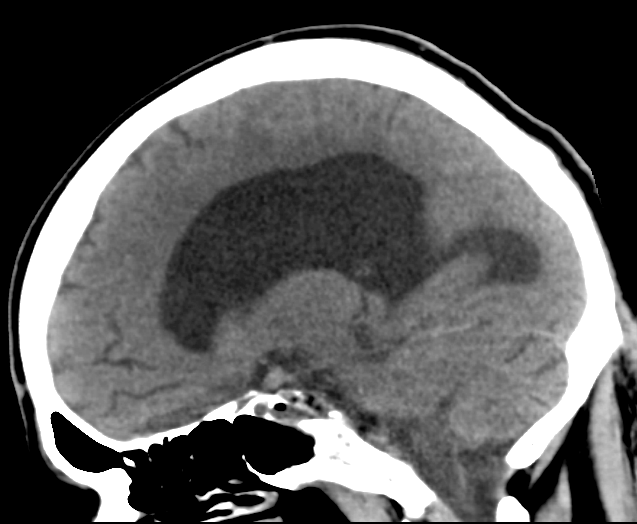

Saggittal CT

One of the key radiographic findings in NPH is enlarged ventricles, out of proportion to cortical atrophy. Remember that generalized brain atrophy can lead to hydrocephalus ex-vacuo, or large appearing ventricles simply as a result of diffuse volume loss. Look at the three images above – in each, the ventricles are much larger than expected.